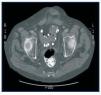

Figura 1. TAC abdominal sin contraste que muestra depósito de carbonato de lantano en los divertículos del colon sigmoides y en recto.

El carbonato de lantano es un quelante del fósforo, libre de calcio y aluminio, de reciente comercialización en España. Se trata de un metal pesado con nula absorción intestinal que no presenta toxicidad. En la ficha técnica del producto en nuestro país, no se cita el fenómeno de aparición de imágenes radiológicas. No ocurre así en la versión americana, donde se advierte que «pueden aparecer imágenes radioopacas en la radiografía abdominal en pacientes consumidores de lantano»1. Las reacciones adversas notificadas con mayor frecuencia fueron gastrointestinales, pero en los ensayos clínicos no se incluyeron pacientes con obstrucción intestinal ni enfermedad inflamatoria intestinal2. Presentamos el caso de un hombre de 58 años, con diverticulosis pancolónica y frecuentes episodios de diverticulitis, con ERC secundaria a nefropatía diabética e inicio de programa de hemodiálisis periódica en abril de 2001. Ingresa en julio de 2008 por fiebre y dolor abdominal. Se realiza una TAC abdominal urgente que descarta signos de diverticulitis, pero es informado por el radiólogo como «restos de contraste en todo el colon e íleon terminal» (figura 1), imagen confirmada en una radiografía simple de abdomen (figura 2). Nuestro paciente no había recibido contraste radiológico en ningún momento, pero estaba siendo tratado con 3.000 mg diarios de carbonato de lantano desde febrero de este año por hiperfosforemia grave, con excelentes resultados analíticos y buena tolerancia clínica hasta el momento. El diagnóstico final fue de sepsis por Enterococo avium, de probable origen intestinal. Dado que no se encontraron otros hallazgos en las pruebas de imagen que justificaran el dolor abdominal, se suspendió el tratamiento con lantano, permaneciendo posteriormente asintomático.